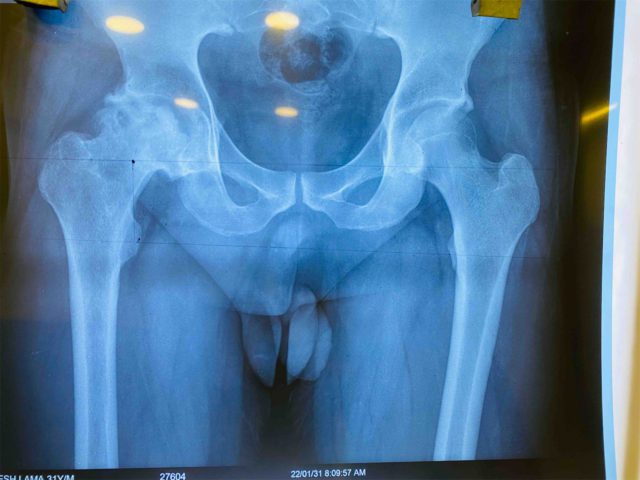

काठमाडौँ, ६ फागुन । बसुन्धारास्थित बीपी स्मृति सामुदायिक अस्पतालमा कम्मरको जोर्नी प्रत्यारोपण (टोटल हीप रिप्लेसमेन्ट सर्जरी) गरिएको छ । गत साता काठमाडौँ धापासीका ३१ वर्षीय युवकको अर्थोपेडिक सर्जन डा. सुनिलसिंह थापा नेतृत्वको टोलीले कम्मरको जोर्नी प्रत्यारोपण गरिदिएको हो ।

सर्जरीको नेतृत्वको गरेका अर्थोपेडिक सर्जन डा. थापाका अनुसार ती युवकमा कम्मरको जोर्नीको गेडिमा रक्तसञ्चार बन्द भई खिइएको अवस्था अर्थात ‘एभास्कुलर नेक्रोसिस’को समस्या थियो । खिईएको भागलाई निकालेर त्यसमा आफूहरुले कृतिम गेडि अर्थात ‘प्रोस्थेसिस’ राखेर शरीरलाई ‘फिट’ गरिदिएको थापाले बताए ।